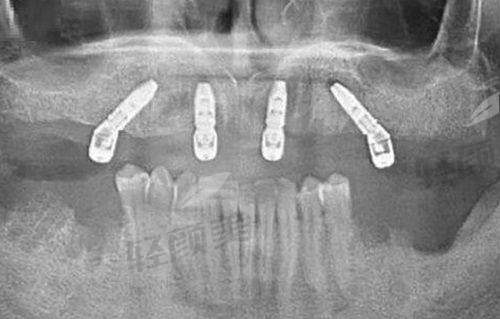

数字化口腔全景机:可以拍摄口腔全景片,清晰显示牙齿、牙槽骨、颌骨等结构的形态和位置。医生通过全景片能够全方面了解患者的口腔情况,为正确诊断和治疗提供依据。

口腔CT:能够提供更详细的口腔三维影像信息,对于复杂的口腔疾病诊断和手术规划具有重要意义。例如,在牙齿种植手术前,口腔CT可以帮助医生正确测量牙槽骨的高度、宽度和密度,选择合适的种植体和种植位置。

牙齿种植:对于缺失牙齿的患者,诊所提供精良的牙齿种植技术。医生会根据患者的牙槽骨情况和身体状况,选择合适的种植体,进行精细的种植手术。牙齿种植后,患者能够修复正常的咀嚼功能,提高生活质量。

其次,诊所注重个性化治疗。医生会根据患者的年龄、牙齿情况、面部特征和个人需求,制定专属的治疗方案。在牙齿种植手术中,医生会根据患者的牙槽骨条件和身体状况,选择合适的种植体和种植方式,确保种植成效的稳定性和美观性。